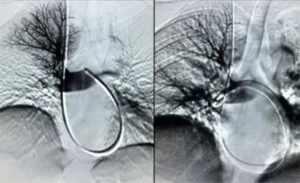

È un “ombrellino” che viene posizionato in vena cava inferiore e serve a proteggere dalla

eventuale migrazione di trombi provenienti dal sistema venoso profondo degli arti

inferiori (in caso di trombosi venosa profonda degli arti inferiori) o dalle vene

iliache e/o dalla vena cava inferiore sotto-renale.Questo può essere posizionato dal Radiologo Interventista sotto guida radiologica, in

maniera abbastanza semplice, sia con approccio dalla vena femorale comune (inguine),

che dalla vena giugulare interna (collo), che dalla vena brachiale (braccio) e dalla

vena poplitea.Questo ombrellino è removibile, quindi nel momento in cui il rischio di migrazione dei

trombi è stato risolto (per esempio quando il Paziente guarisce dalla trombosi venosa

profonda), può essere rimosso dal Radiologo Interventista, sotto guida radiologica, con

accesso dalla vena giugulare interna (collo) e un kit dedicato, fornito dalle case

produttrici del filtro.